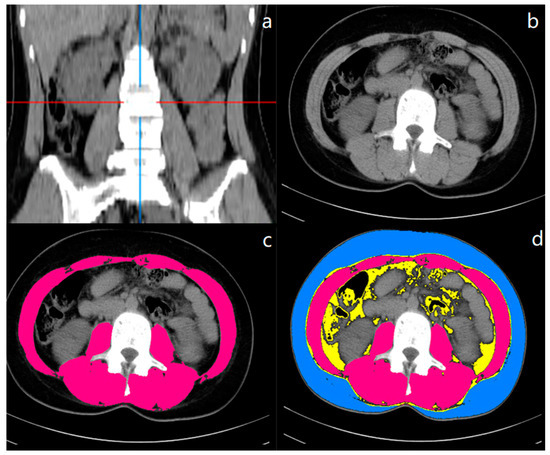

2.3. CT-Based Body Composition Assessment